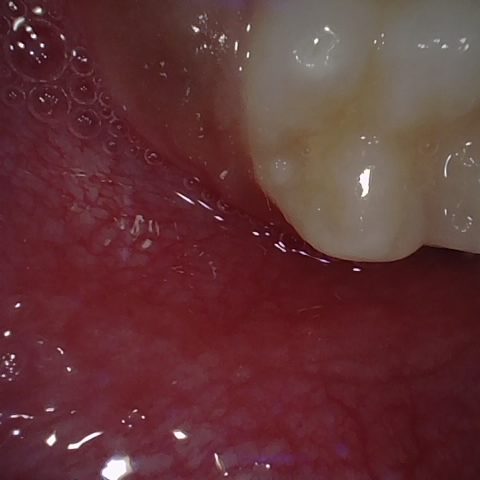

Annotated as "Good"